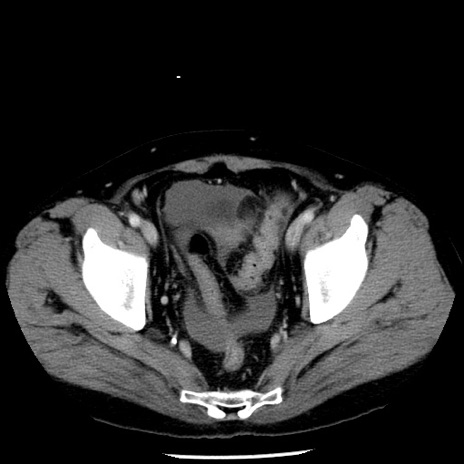

症例29(横断像)

【症例】40歳代男性

【現病歴】2日前から胃痛あり。徐々に周期的な激痛に変化した。本日になっても激痛があるため受診。

【身体所見】意識清明、BT 38-39℃台あり、腹部:膨満、やや硬、右下腹部に圧痛あり。

【データ】WBC 8500、CRP 23.26